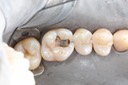

Larry Fujioka #20-21 prep